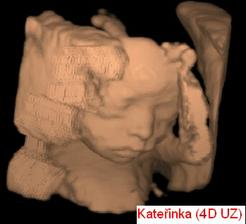

Čekání na Kateřinku... (UZ)

Čekáme holčičku - Kačenku. Dokud jsme jméno vybírali, říkali jsme jí Melounka. I.TP máme 29. 2., II.TP 2. 3. 2008. a III.TP je 13. 3. 2008.